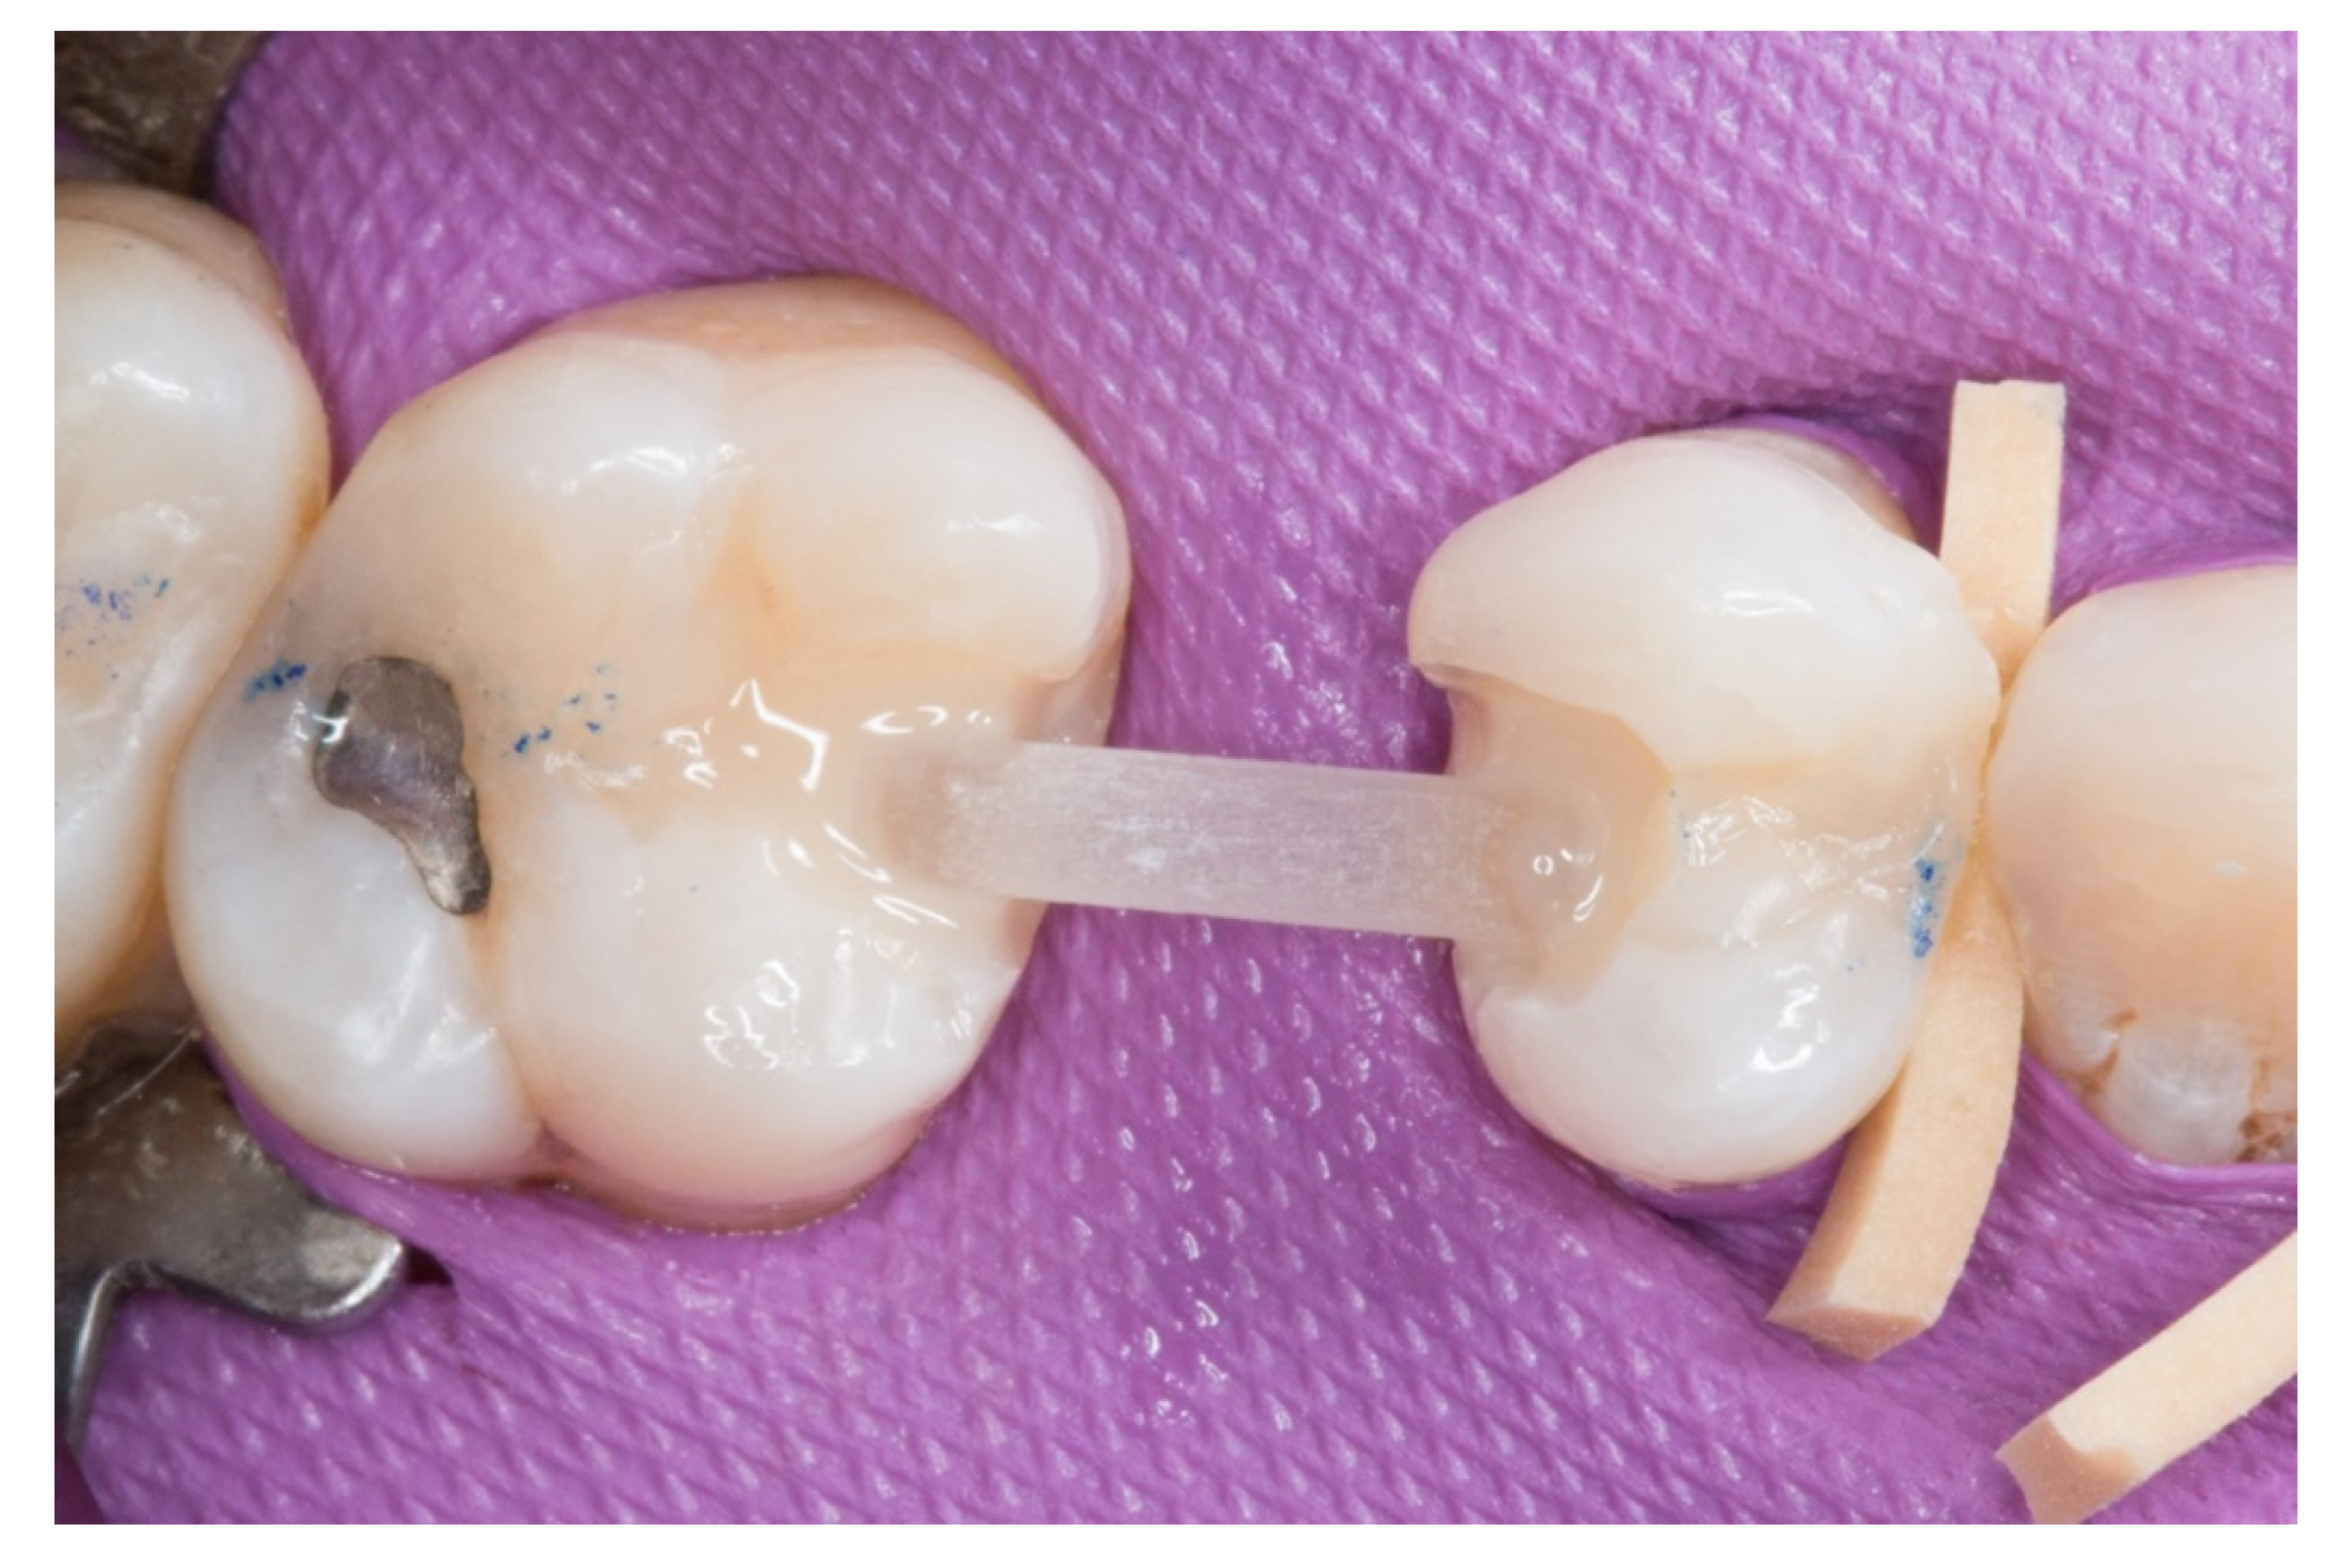

Figure 3.

The transverse structure of the future fiber-reinforced composite bridge (FRCB).

Figure 4.

The horizontal fiberglass pin bonding to the adjacent teeth.

3. The next step consisted of the horizontal fiberglass pin (Rebilda® Post GT, VOCO GmbH, Cuxhaven, Germany) bonding to the adjacent teeth. Firstly, when the isolation of the operative field with the rubber dam was made, the fiberglass pin was adjusted to size and silanization according to the instructions by the manufacturer. Later, the inlay cavities were etched with Ultra-etch® (Ultradent Products Inc, South Jordan, UT, USA) for 20 s, rinsed for 10 s and dried for 10 s. The etched surfaces were covered with a layer of a universal adhesive resin (Prime & Bond® NT, Dentsply Sirona Inc., York, PA, USA), thinned using a brush, and cured for 20 s with a light- polymerizing unit. A flowable resin (Tetric Evo flow®, Ivoclar Vivadent AG, Schaanwald, Liechtenstein) was used to cover the inlay cavities (inlays retainers) and the fiberglass pin to shape the transverse structure of the future bridge (Figure 3 and Figure 4).

4. Afterwards, the pontic core was reinforced with a vertical pin fiberglass structure, which was followed by the same adhesion process mentioned above, obtaining a “T” shape (Figure 5).